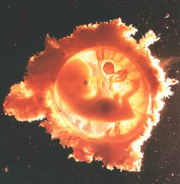

[Das im Blut gelöste

Quecksilber erreicht auch den Fetus / Fötus]

Hg-Dampf vermag ebenfalls die Plazenta-Schranke zu

durchdringen und sich im Embryo bzw. im Fetus anzureichern

(WHO 1991 S.18). Damit ist die Gefahr fruchtschädigender

(S.10)

Wirkungen gegeben (Berlin 1986; siehe unten III. 6. e) ff)

und III. 6. f) jj)).

|

Das Blut

nimmt Quecksilber aus Quecksilberdämpfen auf,

und so kann jedes Organ durch

Quecksilberdämpfe geschädigt werden.

|

Das

ungeborene Leben kann durch Quecksilberdämpfe

schwer geschädigt werden, denn das mit

Quecksilber versetzte Blut erreicht auch den

Fötus.